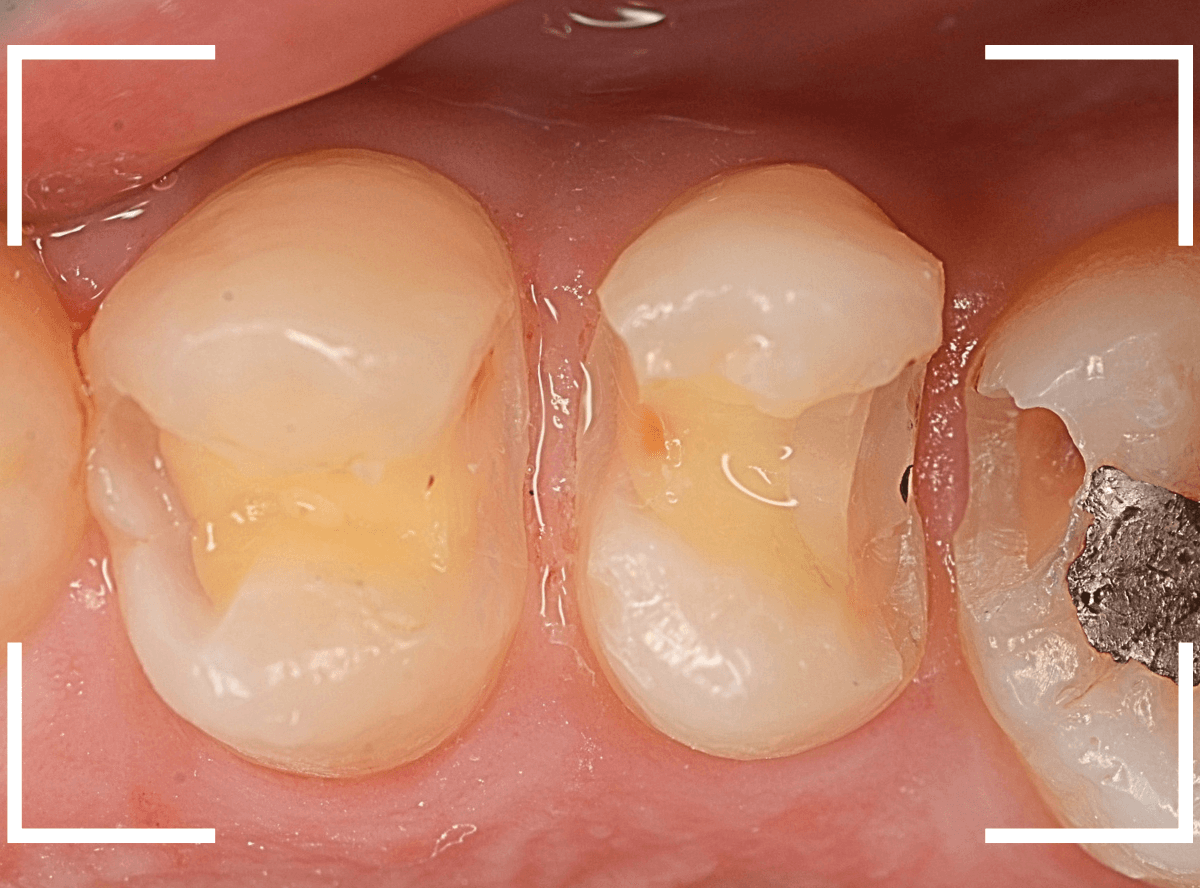

Case.17 レントゲンにはっきり写らないレジンの中の虫歯を削って調べる2

今回も、下の奥歯の虫歯を治療した例です。

特に症状はありませんが、以前に治療したレジンが劣化してすり減っているのと、少し中が黒く透けて見えて、虫歯になっているのが怪しいです。

青いラインが歯の神経です。

以前の虫歯が深めだったようで、レジンが深めにつめてあるのがわかります。

その下がうっすらと虫歯っぽい影になっています(赤いライン)。

虫歯になっているか微妙なラインですが、レジンも劣化していますので、患者さんにご説明して治療することになりました。

レントゲンで虫歯と思われる部分をレジンを除去しました。

見た目には虫歯かどうかはっきりわかりません。

う蝕検知液で染め出します。

うっすらと赤く染色されました。

レントゲン写真と同じく、レジンの下で静かに虫歯が進行し始めていたようです。

もともと深めの虫歯だった部分なので、早いうちに治療が進められてよかったです。

全てのレジンと虫歯を除去しました。

お薬をつめて、症状が出ないかしばらく経過観察します。

歯の外壁部分も薄くなってますので、レジンでは長期保存は難しいと思われます。

今回は、インレーで最終修復する予定です。